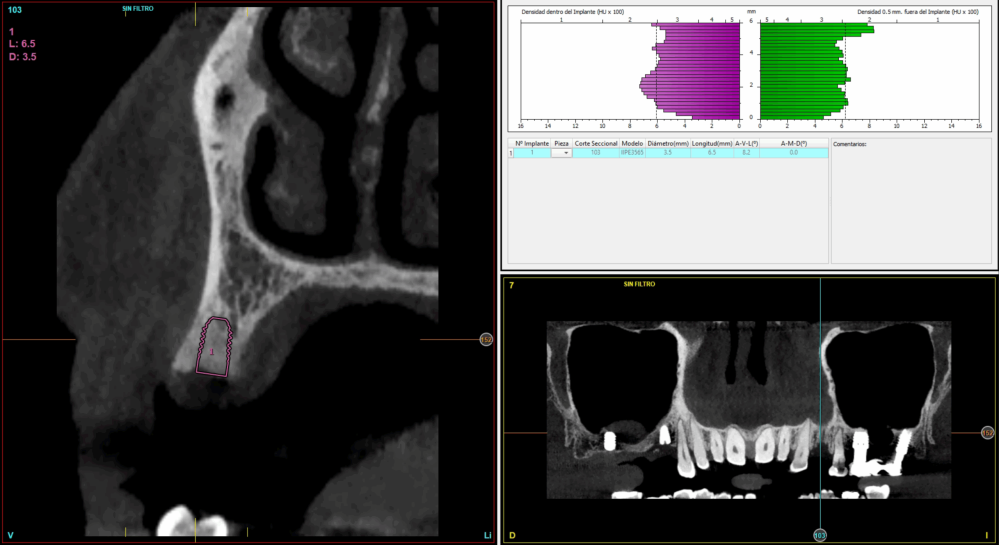

Todas las cirugías fueron realizadas por un único cirujano bajo anestesia local, tras un diagnóstico previo del lecho óseo mediante tomografía volumétrica (CBCT) procesada con un software específico de planificación implantológica (BTI-Scan III). La preparación del lecho implantario se llevó a cabo siguiendo la técnica de fresado biológico a bajas revoluciones descrita por Anitua y cols.19.

Fueron reclutados 21 pacientes en los que se colocaron 21 implantes que reunían los criterios de inclusión anteriormente descritos. Todos los implantes fueron de una longitud de 6,5 mm y el diámetro osciló entre los 3,50 mm el más frecuente con un 66,7% del total, hasta 3 mm en el 14,3%, siendo el restante 19% de diámetro de 3,3 mm. En cuanto a la disposición de los implantes, el 61,8% se situaron en la mandíbula siendo la posición más frecuente en localización de 45 y 46 con un 19% para cada localización. El 38,2% restante se situaron en el maxilar superior, siendo la localización más frecuente en las posiciones de 14 y 15 con un 9,5% cada una de ellas. El resto de las localizaciones se muestran en la Figura 1. El tipo óseo de los implantes insertados fue tipo II en el 66,7% de los casos, de tipo III en el 23,8% y de tipo I en el 9,5%. Si lo distribuimos por regiones anatómicas el más frecuente para el maxilar fue el tipo II (60%) y para la mandíbula también (54,5%). La distribución de los tipos óseos en función de la región se muestra en la Figura 2. El torque medio de inserción de los implantes fue de 37,14 Ncm (+/- 14,54). Los torques en función del tipo óseo y la localización anatómica se muestran en las Figuras 3 y 4. En 11 de los pacientes se llevó a cabo una carga inmediata, y en el resto una diferida.